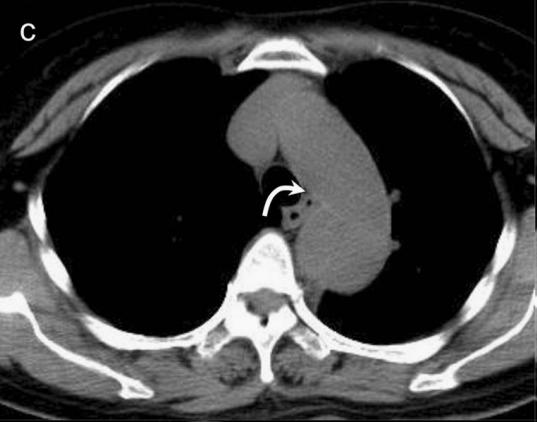

病例7

你看,我家的CT这么模糊,平扫怎么看主动脉夹层?

图18

不焦急!仔细看,血管里面的“血液”居然钙化了!这叫血管钙化内移,要警惕主动脉夹层!有研究发现,血管钙化内移诊断动脉夹层的特异性高达90%。

图19

赶紧做个增强CT!主动脉裂开了!

图20